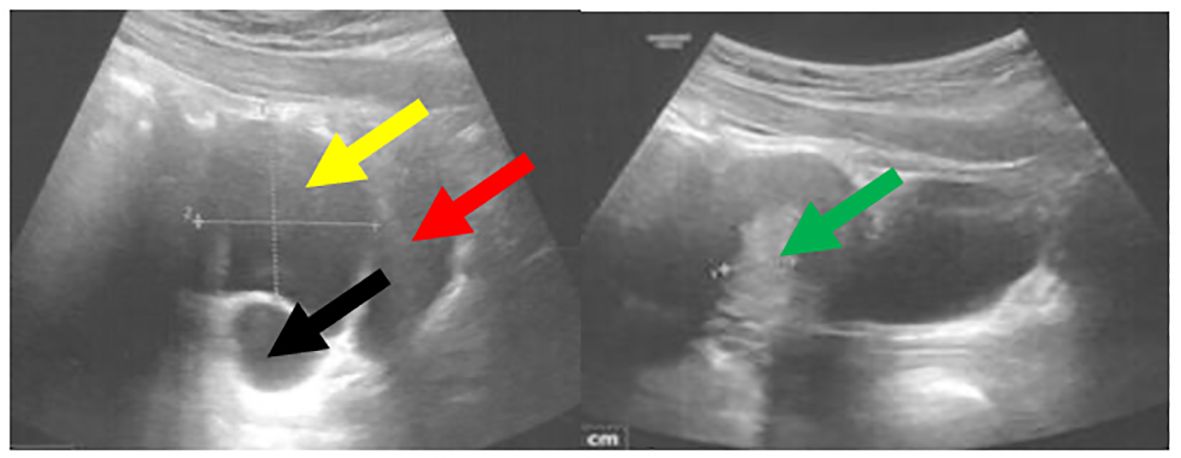

Figure 5. Pelvic ultrasound performed at 13 years and 8 months of age demonstrated a cyst within the right ovary measuring 5 × 4 cm. The bladder is indicated by the red arrow, the uterus with an endometrial thickness of 13.3 mm by the green arrow, the cyst by the yellow arrow, and the right ovary by the black arrow.

During a control visit at the age of 7 months the disappearance of renal cysts was noted, and the structure of kidneys appeared normal. At the age of seven years and two months, the episodes of abdominal pain occurring mainly in the evenings, resolving spontaneously or after bowel movements have been reported. Physical examination was unremarkable, and lab tests were within normal limits. An abdominal USG revealed a gallbladder containing a 3.5 mm echogenic structure with a weak acoustic shadow, consistent with a gallstone, leading to a diagnosis of cholelithiasis without signs of inflammation. Treatment with ursodeoxycholic acid was initiated, with recommendary dietary modifications. Over the following year, she continued to experience intermittent abdominal pain. At eight years old, she performed a hydrogen breath test with lactulose that indicated small intestinal bacterial overgrowth (SIBO) treated with metronidazole for ten days, followed by a probiotic regimen. Despite initial improvement, abdominal pain recurred even though subsequent hydrogen breath test with lactose was negative, ruling out lactose intolerance. Further gastrointestinal evaluation did not reveal additional pathology. The recurrent abdominal pain and diagnosis of SIBO suggested that gastrointestinal dysmotility or altered gut flora might be contributing factors. Pubertal development commenced at 7 years and 3 months of age, with thelarche at Tanner stage II observed. Consequently, the hydrocortisone dose was increased to slow the progression of puberty. Suppression with a GnRH analogue was not initiated, as the bone age remained within normal limits (advanced by no more than one year relative to chronological age). Menarche occurred at 10 years and 7 months. Initially, menstrual cycles were irregular and heavy, necessitating gynecological follow-up. Conservative management was implemented with tranexamic acid (Exacyl) and etamsylate (Cyclonamine). A follow-up pelvic ultrasound revealed a 4 cm ovarian cyst, prompting the initiation of dydrogesterone therapy from day 16th of the menstrual cycle for 10 days each month. As presented in the Table 4, dydrogesterone has been effective in controlling ovarian cysts. However, in our patient, ovarian cysts have recurred alternately in both ovaries, reaching sizes of up to 5 cm (Figure 5). If this issue persists, we plan to initiate treatment with an oral contraceptive pill.